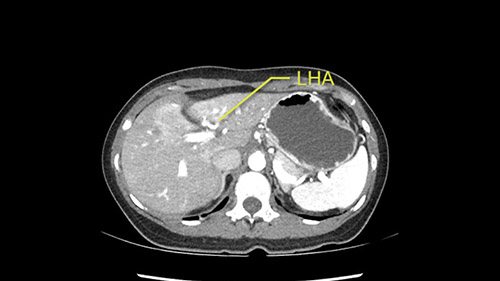

Inflow is not usually an issue except if there are as a replaced or aberrant left hepatic artery. In which case you’d be careful when you mobilize the left lateral segment.

So I have to say that I would do this open, not laparoscopically because of the size of the tumor itself. Upper abdominal incision. Almost certainly, we’d be able to flip this very exophytic lesion up. Intraoperative ultrasound will show the relationship of the tumor and the left portal vein but the dissection at the base of the liver, as I look at things here, I can see the left hepatic artery which sneaks up to the left of the portal vein, should be out of harm’s way so I can take the Segment 2-3 left hepatic artery. The left portal vein is somewhat compressed. But by the time you pull the liver up a bit, you’ll be able to pull that left portal vein out to length and get a good margin on it.

The second is the left hepatic artery. The tumor is displacing the arterial system. So one of the important points which we need to see intraoperatively is to identify and preserve the right artery very carefully and identify the left hepatic artery for ligation.

So in planning for this operation, as I look at the scans, I first visualize the arterial phase and I can see that there’s are a lot of big feeding arteries to this large tumor. Likely all the right side vessels feeding the right side of the liver: right hepatic artery and likely the Segment 4 artery are spared from the tumor. It’s likely the left hepatic artery is ramificating and giving feeding arteries to this tumor. It certainly looks like a large mass that its compressing other structures like the cava, the pancreas, the stomach; but I think there’s a plane and we can see that better in the venous phase. There’s a plane of separation between the gallbladder, the pancreas, the cava, that this tumor is abrupting but likely not invading. Usually, these masses actually don’t invade at that level and basically are pushing the tissues and once you open, you’re able to separate the tumor. Sometimes there’s some adhesions but you can actually separate and there’s usually no invasion.